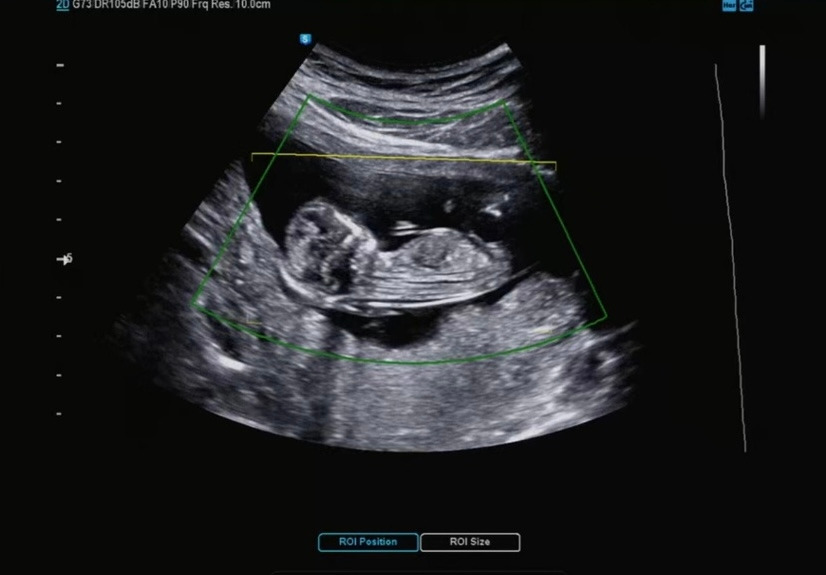

12주 차 검사에서는 원래 손가락 개수, 발가락 개수 확인을 안 한다고 하셨다.

하지만 선생님께서 봐주셨다. 하나 둘 셋 넷 다섯.. :)

조곰한 다올이가 이제 형체가 하나하나 생겨가고 있다. 뇌도 보고 위도 보고 심장도 보고 심장소리도 듣고 왔다. 우리 아가를 자꾸 발을 꼬고 있는다. 내가 발을 잘 꼬고 있어서 (?) 그런 건가??라는 생각이 들었다.

KakaoTalk_20220504_095501433.jpg 허벅지 종아리 발

그리고 1차 기형아 검사에서 목 투명대를 봐준다. 다행히 정상범위에 있었다. 모든 게 다 정상범위에 있어서 다행이라고 생각했다 :)